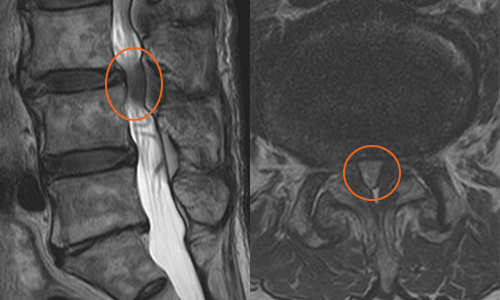

환자 : 82세 남성 증세 : 제 3,4번 요추간 비후된 황색 인대

경과 : 비후된 황색 인대가 제거된 결과, 비정상적인 신경의 신호가 하얗게 호전되고 신경근도 선명하게 드러남